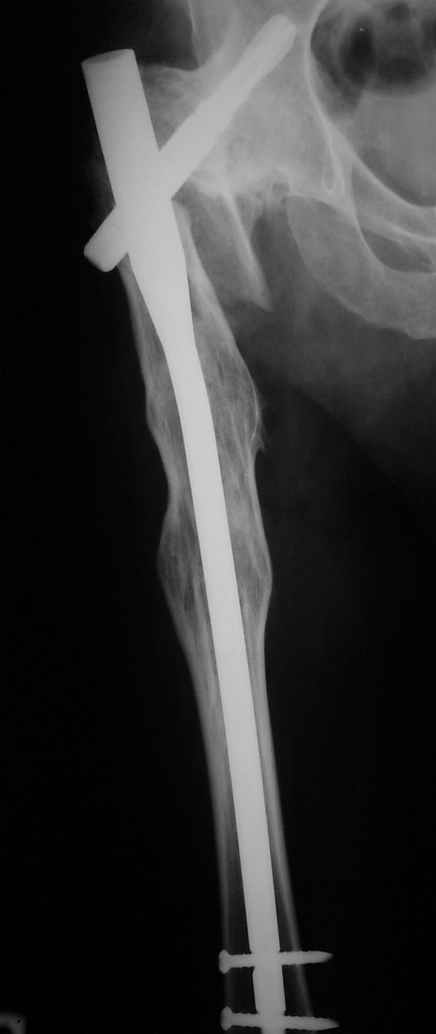

Месяцев 6 назад оперировали такого больного (анкилоз после туберкулезного коксита 40 ле назад) интрамедуллярным стержнем PFNa. Ушел на своих ногах (с тростью кончно, как и до травмы). Больше не появлялся.

Рентгенограммы до и после. Больной профессор на кафедре сопромата и после детального изучения

особенностей имплантата, собственных рентгенограмм дал добро на операцию. Ваш вариант лечения вполне симпатичен.